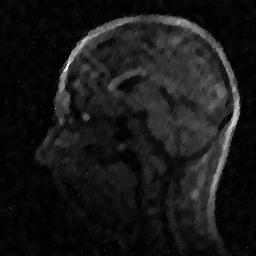

6.3. MR Image reconstruction

The second imaging application is concerned with medical imaging. Following the ideas from [32, 34], we simulate a multi-channel MRI sensing set-up, first using the same sine waves as in the previous experiment (results displayed in Fig 10), and then using spherical beam pattern (see in Fig. 11 for the results). We generate the classical Shep-Logan phantom, and set its dimension to .

The first experiment, depicted in Fig. 10 shows the results obtained by our method when using a Daubechies 4 sparsifying dictionary. Our results are compared to the single sensor analysis, and the results obtained by the Sum-of-Squares recovery [34, 32].

The recovery is obtained from noisy measurements, in which some additive Gaussian noise with variance has been added. The measurements are obtained by subsampling ( samples) of the Fourier transform. We see here that the fused compressed sensing is better capable of handling a multi-channel problem with unusual illumination (compared to the Sum-of-Squares method). Moreover, more details are preserved, when compared to the single sensor analysis method.

Some noise still appears in the image, but can easily be thresholded further if needed. One important aspect of MR Images that hasn’t been considered in this research, is the fact that they are sparse in gradient. One usually prefers to minimize the Total Variation instead of the norm or another frame using analysis.

Although we have not explicitly written the theory here, the recovered images in Fig. 11 show the results when using a TV minimization instead of the analysis.

The results were obtained from a spherical beam illuminating the input image. The measurements are obtained by sampling ( samples) of the Fourier coefficients at random iid from a Gaussian distribution. Again, some Gaussian noise with variance is added to every measurements.

As presented in these examples, our method is capable of handling highly complex signals in potentially many dimensions yet keeping a very low number of samples taken. We can also empirically verify that the presented approach enjoys more robustness to noise and variations in scene illuminations than other known methods.

This behavior is true for both images, which are real-world images of brain scans. It is worth keeping in mind that SSIM is a structural similarity which tries to emulate the human visual perception while the other metrics are pure machinery. As can be seen both from the figures and the tables, the proposed method performs at least as well as previous approaches, and may behave better when considering total variation minimization.